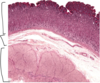

Rectum -

rectum is the terminal portion of the sigmoid colon, and therefore, it is similar in structure to the colon. At the macroscopic level, this area has longitudinal folds called rectal columns. The mucosa contains numerous goblet cells, and the submucosa may have hemorrhoidal venous plexuses which can extend into the lamina propria. The mascularis externa has

both inner circular and outer longitudinal smooth muscle layers. Arrows: some of the blood channels.